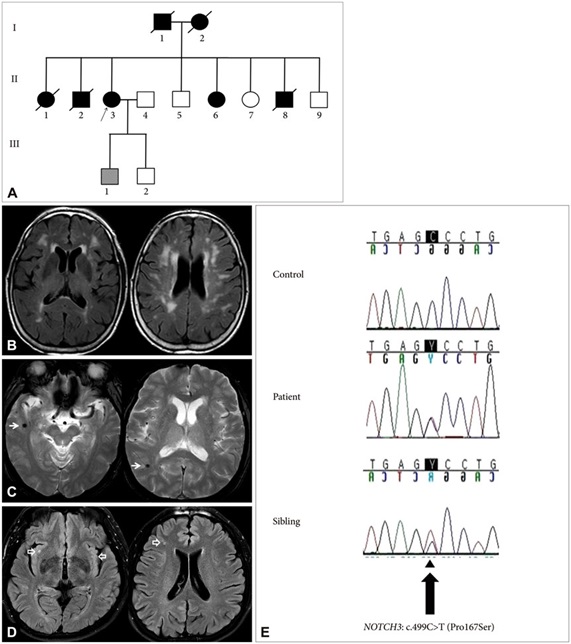

Figure 4. Schematic view of the pattern of inheritance in NOTCH3 gene mutation in patients with migraine and controls with brain scans